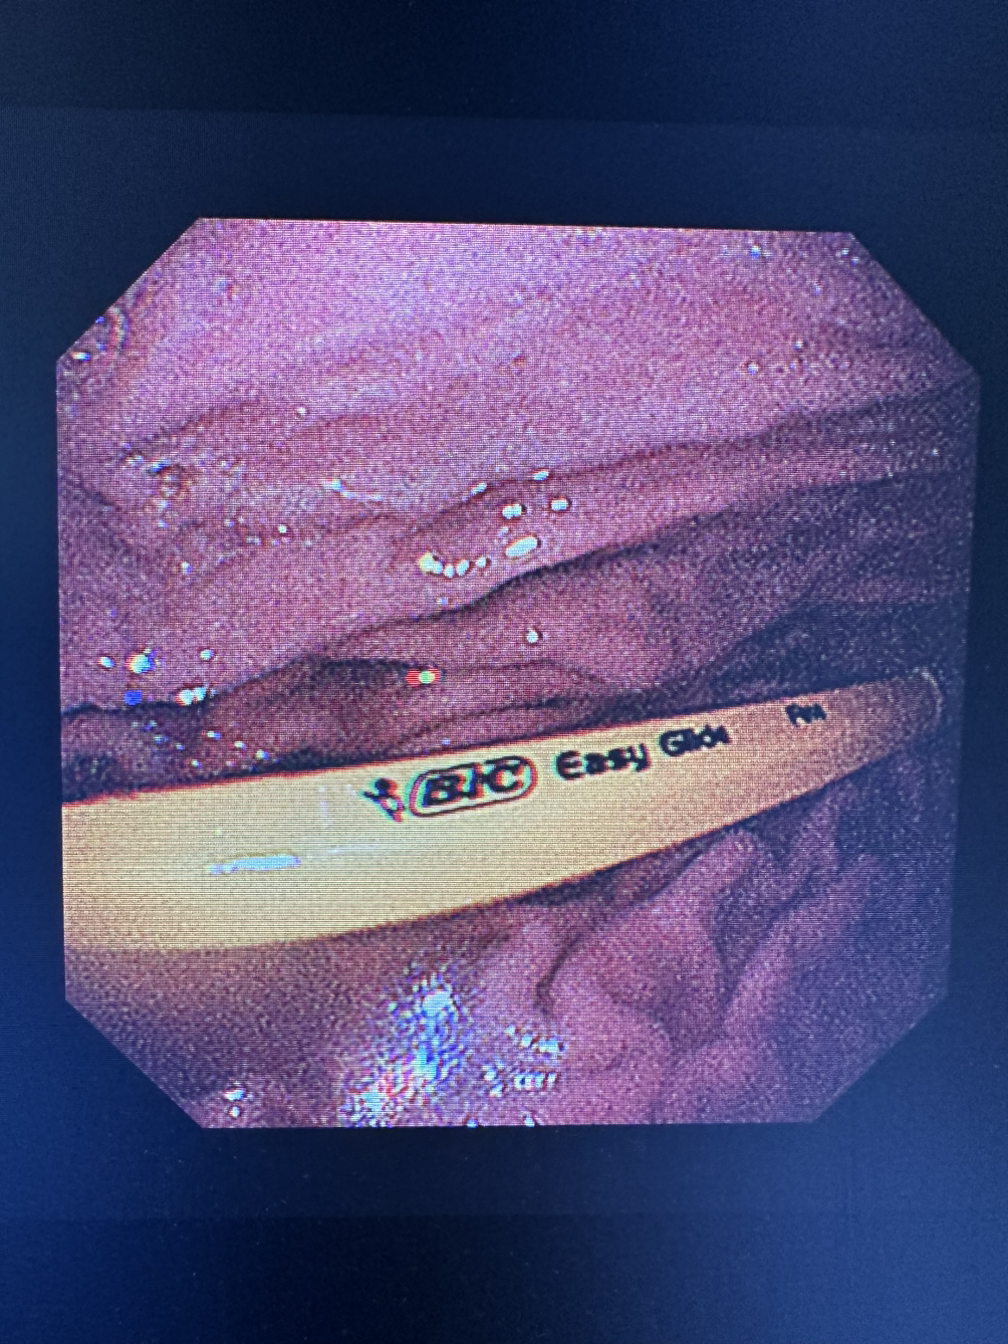

몇 개월 동안 뺐던 생선 가시들이다. 얼핏 보면 커 보이지 않지만 pyriforn sinus(이상와)의 크기보다 큰 이물들은 나오면서도 상처가 생길 수 있고 식도에도 상처를 입힌다. 몇 년 전, 생선 가시가 식도에 박혀있는 환자가 종합병원에서 내시경을 하고 응급실로 왔었다. CT상엔 동맥에 1/3이 침범해 있었고 가시가 박혀 있는 주변부는 농이 나오고 있었다. 다음날 수술실에서 흉부외과와 조인해서 내시경을 했다. 우리가 내시경으로 가이드를 하고 가시를 제거하면 출혈을 잡지 못할 것이기에 개흉수술을 바로 진행할 예정이었다. 다행히 출혈은 심하지 않았고 내시경적으로 해결할 수 있었지만 그 아찔함이란. 그만큼 생선가시를 삼키면 위험하다. 김치나 밥을 삼켜 빼는 것보단 내시경적으로 제거하는 것이 바람직하다.